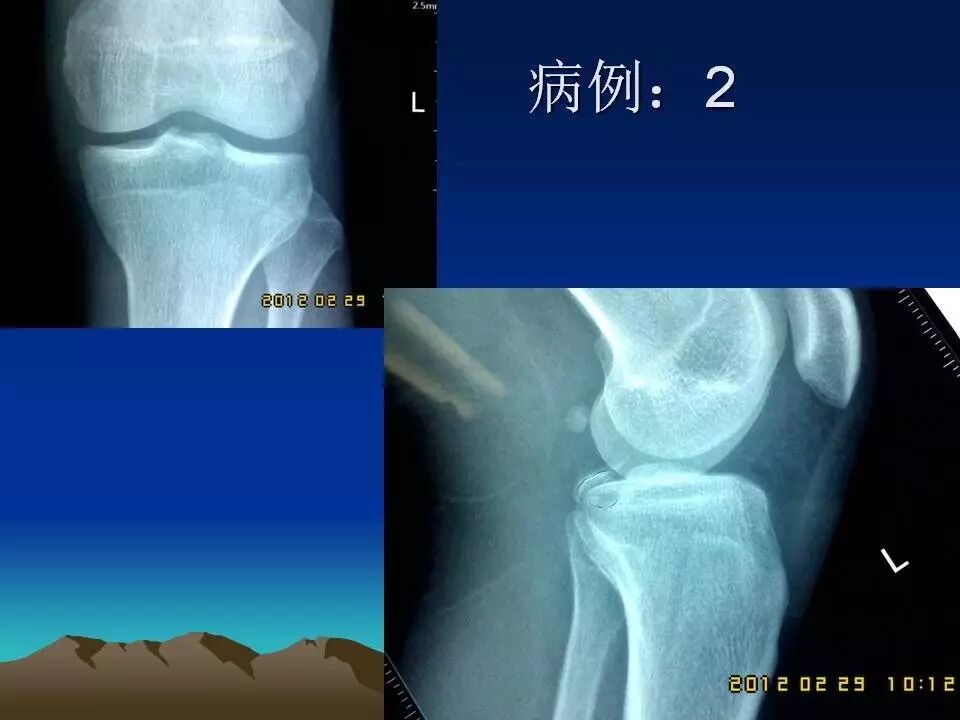

前十字韧带是膝关节重要的前向稳定结构,断裂后可以产生明显的膝关节不稳,严重影响膝关节功能,如果不及时治疗,关节出现反复扭伤,容易引起关节软骨、半月板等重要结构的损害,导致关节过早老化和骨关节病的发生。